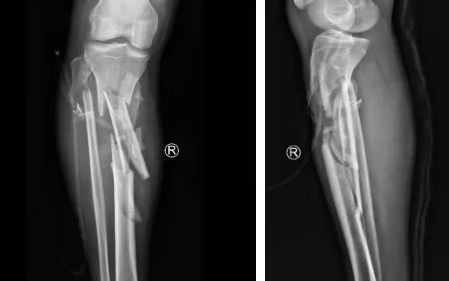

小张一场意外车祸导致小腿胫骨粉碎性骨折,在必威官方首页官网betway进行了骨延长手术,得知曹广超主任来看望他后,早早来到门口等待。

胫骨粉碎性骨折,伴有腓总神经损伤

骨延长术后